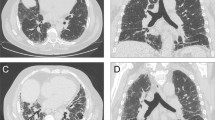

A UIP pattern related to ARDs in some cases displays imaging features that distinguish it from a UIP pattern related to IPF; specifically, the “straight-edge” sign, the “exuberant honeycombing” sign and the “anterior upper lobe” sign are suggestive for an autoimmune background [31].

The “anterior upper lobe” sign is defined as concomitant fibrosis with honeycombing in the anterior part of the upper lobe combined with a UIP pattern consisting of reticulation and honeycombing in a predominantly basal distribution (Fig. 2A). It is found in 25.4–34.9% of patients with ARD-UIP compared to 12.8–17.2% of patients with IPF-UIP.

Radiological ancillary findings in ARDs-related UIP pattern A) Marked honeycombing/reticulation both primarily in the lower lobe. However, a distinct “anterior upper lobe” sign is visible (white arrow) in a patient with RA-UIP. B) “Straight edge” sign with in a patient with polymyositis related UIP pattern. C) Axial image from the same patient as A, both the axial and sagittal images have almost exclusively honeycombing representing the “exuberant honeycombing” sign

The “straight-edge” sign is a markedly sparing of the upper and midzones from fibrosis with a sharp horizontal demarcation between the fibrotic and normal lung parenchyma (Fig. 2B). Furthermore, the fibrosis does not extend cranially along the lateral chest wall. Patients with ARD-UIP exhibit the sign in 25.4–36.0% of the cases, whereas only 6.0–8.3% of patients with IPF-UIP [31]. The “straight-edge” sign is associated with an increased survival, mainly in patients where the sign is found in combination with IPF-UIP. It has been suggested that this could represent a certain phenotype of IPF.

The” exuberant honeycombing” sign is characterized by more than 70% of the fibrotic lung and it is made up by honeycomb cysts (Fig. 2C). This sign can be described in 22.2% of patients with ARD-UIP compared to 6.0% with IPF-UIP.